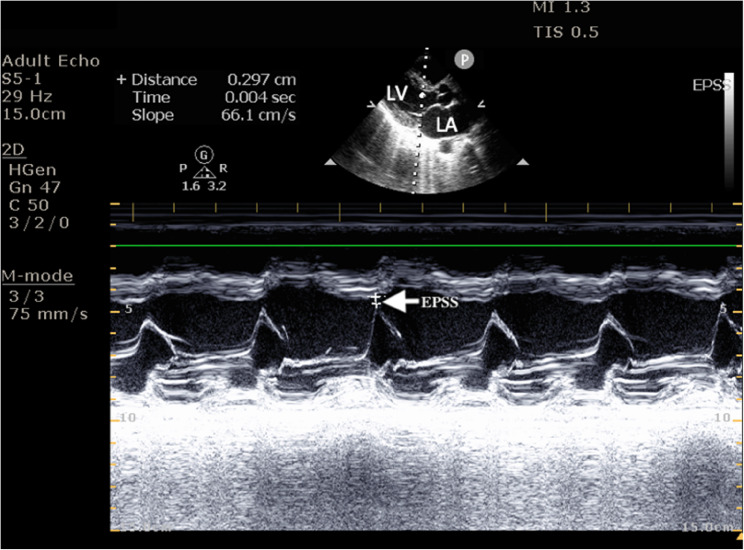

Background: Post-intubation hypotension (PIh) is a frequent complication following drug-assisted intubation, leading to increased morbidity, mortality, and healthcare costs. Pre-intubation hemodynamic factors, acid-base imbalances, and existing comorbidities, particularly right ventricular dysfunction, which is a lesser-known variable, have emerged as a critical predictor of PIh. Since RV systolic motion is predominantly longitudinal, TAPSE on POCUS provides a time-sensitive surrogate of RV function for high risk patients in the Emergency department.

Methods: Aim: The study aimed to list hemodynamic predictors and their correlation with easily executable POCUS and point-of-care echocardiography variables, which can impact emergency decision-making and optimal management in PIh. This prospective observational study was conducted in the Department of Emergency Medicine at Kasturba Medical College, Manipal, Manipal Academy of Higher Education, Manipal, Karnataka, India. 172 patients aged ≥ 18 years undergoing drug-assisted intubation were observed. Baseline demographics, clinical parameters, hemodynamic indices, and pre-intubation echocardiographic values (TAPSE, EPSS) were recorded. Shock index and modified shock index were calculated. Point-of-care ultrasound (POCUS) assessed left and right ventricular function. PIh within 30 min was defined as SBP [Formula: see text] 90mmHg, ≥ 20% fall in SBP, MAP < 65mmHg or new vasopressor initiation. Associations were tested with logistic regression. TAPSE discrimination was obtained with ROC analysis and Youden's Index.

Results: Of the 172 patients, 71 (41.2%) developed PIh. Patients with obstructive lung disease (59.3%, p = 0.039) and sepsis (66.7%) were significantly more likely to experience PIh. TAPSE values were significantly lower in those with PIh (17.66 ± 2.45 mm vs. 18.54 ± 2.15 mm, p = 0.014). The multivariate logistic regression revealed TAPSE as an independent predictor of PIh (OR = 0.81, 95% CI = 0.69-0.95, p = 0.009). ROC analysis of TAPSE showed moderate predictive power (AUC 0.584, 95% CI 0.497-0.672), with a cut-off of 17.6 mm (sensitivity 85.1% and specificity 29.6%).

Conclusion: TAPSE measured pre-intubation emerged as a reliable predictor of post-intubation hypotension. Incorporating a rapid assessment of right ventricular function using POCUS into the airway management algorithm provides valuable insights in identifying patients at higher risk of PIh.